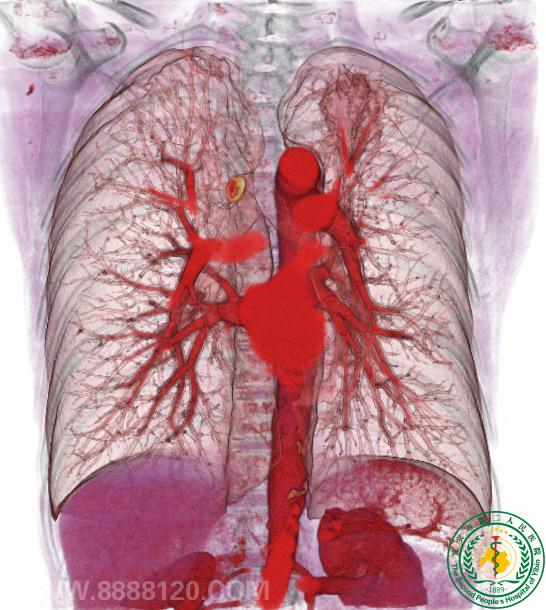

64排螺旋CT优秀后处理图片展示

胸部重建                  左上肺肿瘤与肺血管